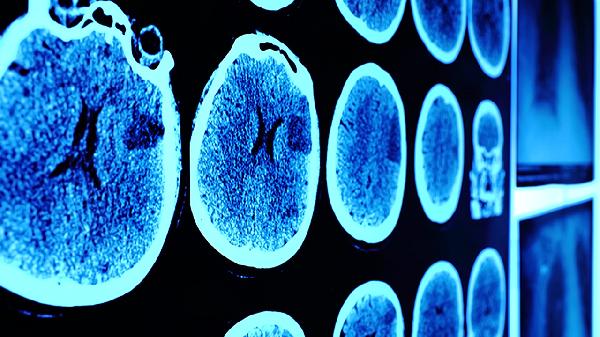

受傷后可能出現(xiàn)數(shù)秒至數(shù)分鐘的意識模糊,表現(xiàn)為對時(shí)間、地點(diǎn)或人物的定向力障礙,無法回憶受傷經(jīng)過。這種一過性意識障礙與神經(jīng)元電活動(dòng)短暫紊亂相關(guān),通常自行恢復(fù)但可能遺留記憶空白。出現(xiàn)此類癥狀時(shí)須密切觀察24小時(shí),警惕遲發(fā)性顱內(nèi)血腫。醫(yī)生可能建議進(jìn)行頭顱CT檢查以排除嚴(yán)重?fù)p傷。